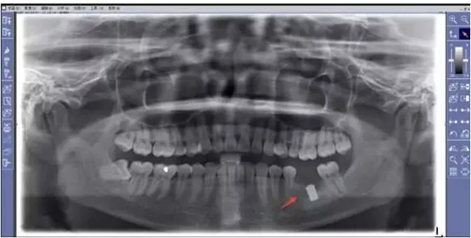

NO.1先要做一个口腔全景片、颌骨CT等医生根据机器成像查看口腔的具体情况,是否有炎症、牙槽骨的密度、吸收状况以及邻牙组织、牙体组织等。

注明:此数据仅作模拟,不是确切种植数据。

如果仅靠双眼大致估测口内数据,是无法得到精准的高度、宽度的,也无法确认骨头吸收多少,是否需要植入骨粉。对后期手术有一定的影响。通过全景片可以“解剖”牙齿精确测量,适宜的种植角度也可确定,健康安全有保障。